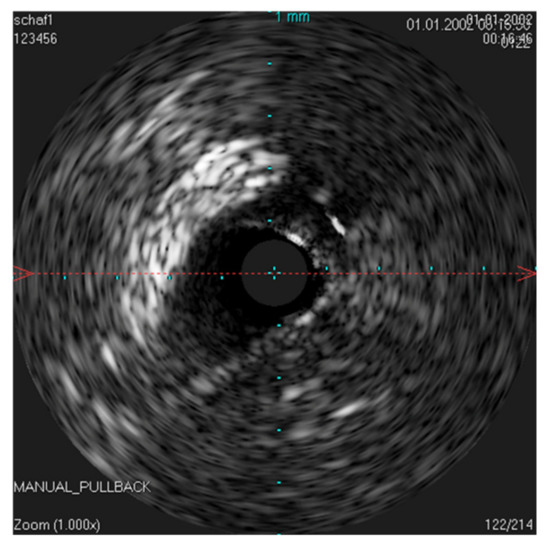

In order to possibly investigate the function of the ET, the lower jaw was moved manually during scans with a stationary IVUS catheter in the ET. An extension of the lumen and, thus, a size change of the lumen could be visualized (Figure 9) in the time-based longitudinal view. With the lower jaw closed, a lumen size of 3.21 mm2 was measured. The probe itself had a size of 1.33 mm2. With the mandible open, this lumen increased to 3.75 mm2. In the longitudinal view, this repetitive size change was clearly visible as waves.

Figure 9. Ultrasound image of the ET with a stationary IVUS probe. During the scan, the lower jaw was repeatedly moved manually, thus opening and closing the sheep’s mouth. Image (A) shows the ET over time. The lumen changes and movements of the surrounding structures can be seen as waves. Part (B) shows the cross-section of the tube with the mouth open, with an approximate tube lumen of 3.75 mm2, where the probe has an area of 1.33 mm2. Part (C) shows the same area with the jaws closed, where the tube lumen has decreased to 3.21 mm2.